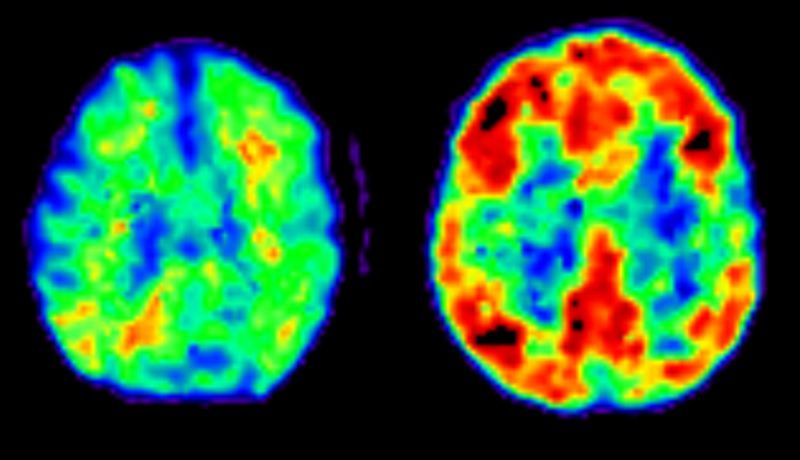

Alzheimer seringkali didiagnosis berdasarkan sejarah klinis pasien, pemeriksaan fisik, serta tes pencitraan otak seperti MRI atau PET scan.